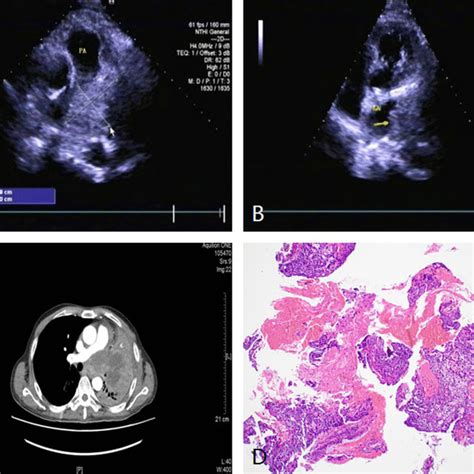

The diagnostic approach to a hilar lung mass begins with imaging. Chest X-rays can provide an initial indication of a mass, but CT scans offer more detailed information about the mass's size, location, and potential invasion into surrounding structures. PET scans can help assess the mass's metabolic activity, which is useful in distinguishing benign from malignant lesions and identifying potential metastases. Ultimately, a tissue diagnosis through biopsy is necessary to determine the mass's nature and guide treatment.

Diagnosing a hilar lung mass typically involves a combination of imaging studies, such as chest X-rays, computed tomography (CT) scans, and positron emission tomography (PET) scans, along with biopsy and histopathological examination to determine the nature of the mass. Symptoms can vary widely depending on the size, location, and nature of the mass, as well as the patient's overall health. Common symptoms include cough, chest pain, shortness of breath, and in some cases, systemic symptoms like weight loss or fever if the mass is malignant or infectious in origin.